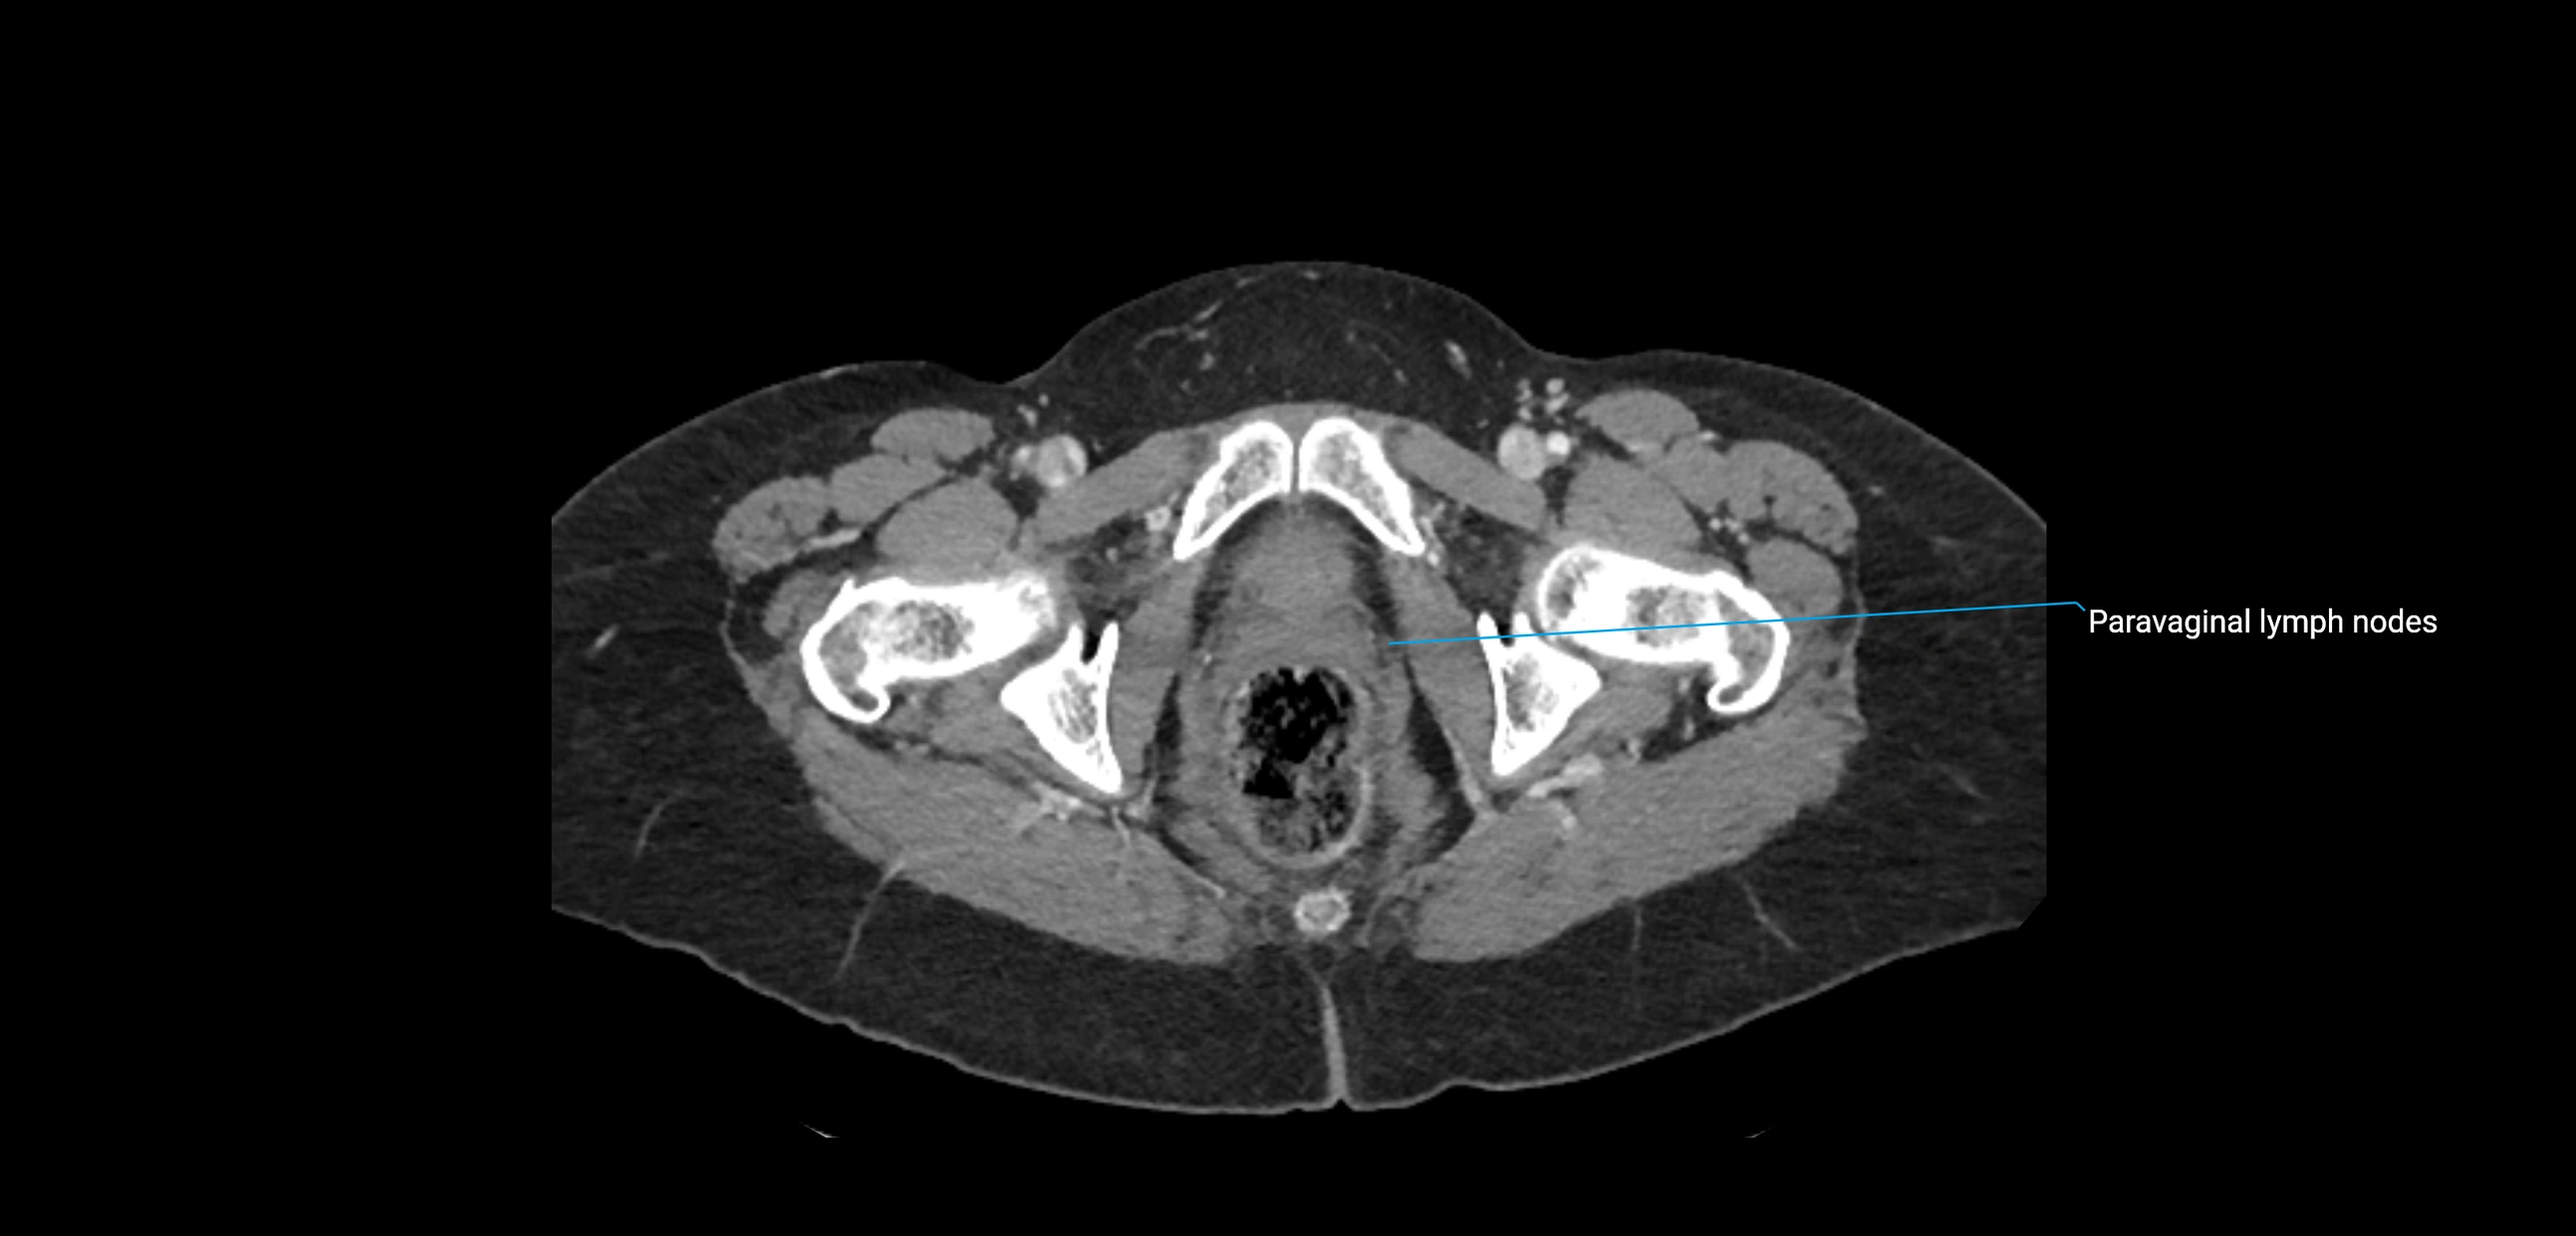

CT Appearance

CT Post-Contrast:

• Normal nodes enhance homogeneously

• Malignant nodes may show heterogeneous enhancement, central necrosis, or conglomerate formation

• Size >1 cm short axis is suspicious, though morphology and distribution are equally important